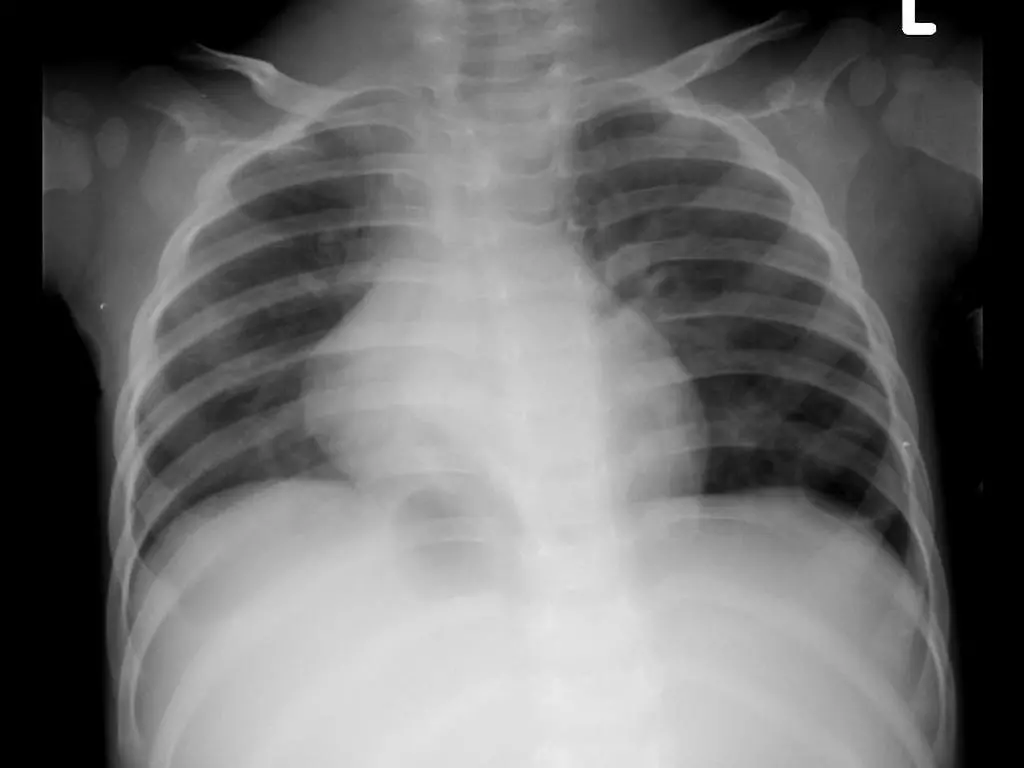

Quais os achados radiológicos mais comuns na pneumonia comunitária?

Infiltrado pulmonar do tipo alveolar broncopneumônico com presença de broncograma aéreo